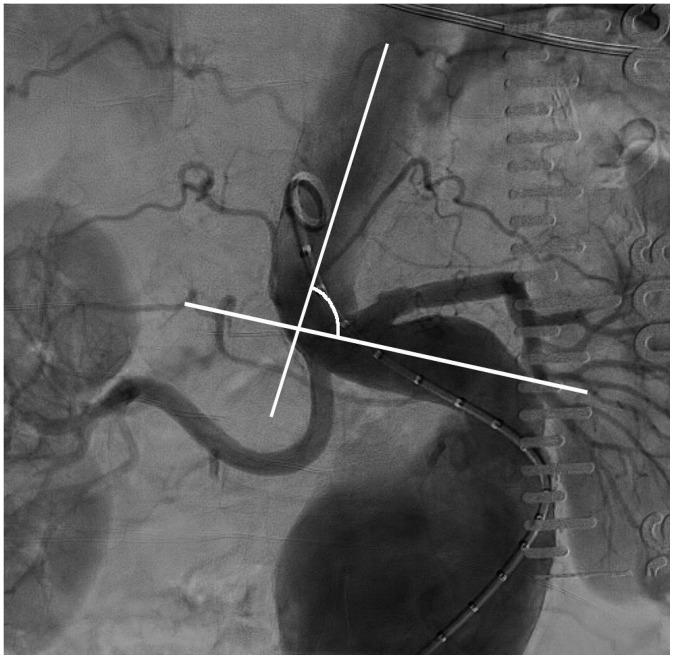

Endovascular Aneurysm Repair for Abdominal Aortic Aneurysm: A Comprehensive Review.

Abdominal aortic aneurysm (AAA) can be defined as an abnormal, progressive dilatation of the abdominal aorta, carrying a substantial risk for fatal aneurysmal rupture. Endovascular aneurysmal repair (EVAR) for AAA is a minimally invasive endovascular procedure that involves the placement of a bifurcated or tubular stent-graft over the AAA to exclude the aneurysm from arterial circulation. In contrast to open surgical repair, EVAR only requires a stab incision, shorter procedure time, and early recovery. Although EVAR seems to be an attractive solution with many advantages for AAA repair, there are detailed requirements and many important aspects should be understood before the procedure. In this comprehensive review, fundamental information regarding AAA and EVAR is presented.